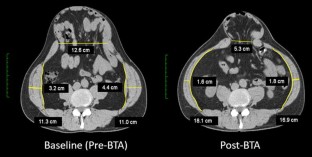

Thirty-two patients received BTA injections which were well tolerated with no complications. A comparison of baseline (preBTA) CT imaging with postBTA imaging demonstrated an increase in mean baseline abdominal wall length from 16.4 to 20.4 cm per side (p < 0.0001), which translates to a gain in mean transverse length of the unstretched anterolateral abdominal wall muscles of 4.0 cm/side (range 0–11.7 cm/side). Fascial closure was achieved in all cases, with no instances of raised intra-abdominal pressures or its sequelae, and there have been no hernia recurrences to date.